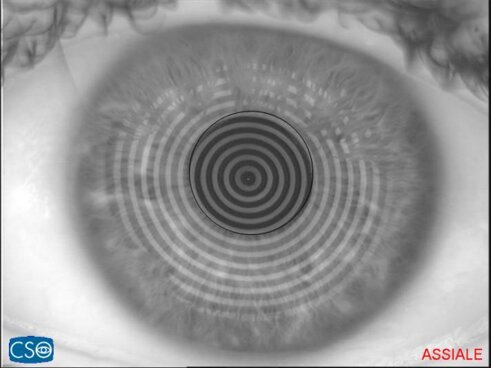

CHERATOCONO

Malattia degenerativa della cornea che diventa progressivamente più sottile e assume una forma irregolare. Determina un peggioramento della qualità visiva, soprattutto nei giovani.